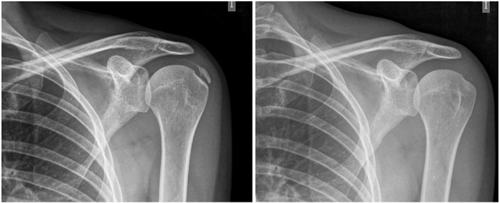

Figure 1

Figure 2